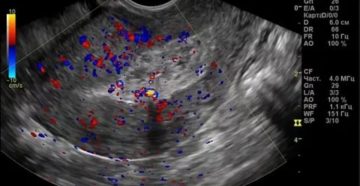

Почему на УЗИ не видно беременности? А тест положительный » УЗИ при беременности » Достаточно…